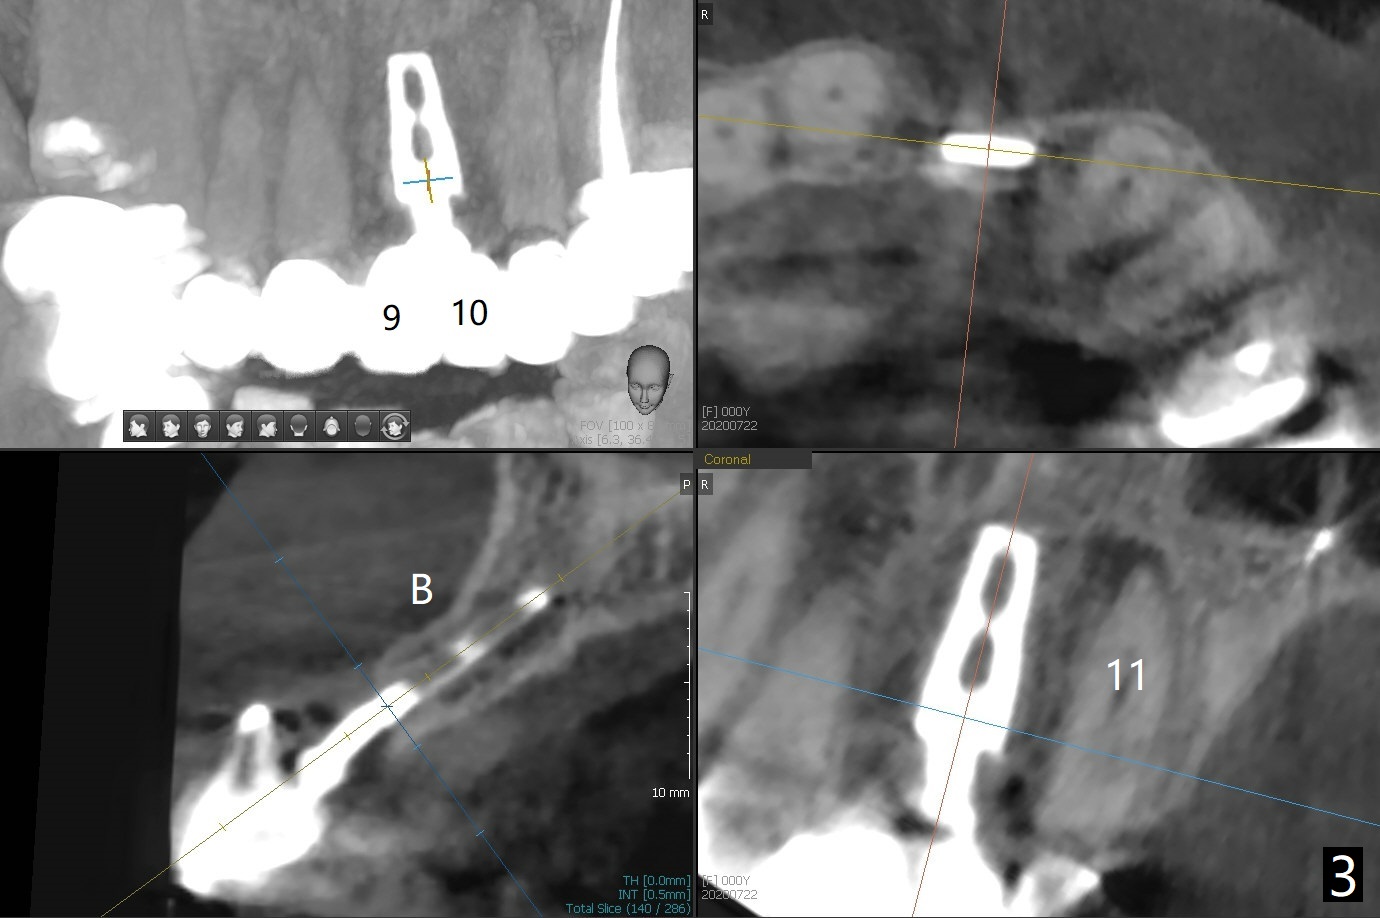

今天来一位57岁女,“前牙桥快掉了” (图一:7-11,桥在尖牙(11)端松动明显),不明白为什么左上中,侧切牙唇侧带有托牙树脂(*),影响局部卫生(^)。全景片(图二),CT(图三)显示刀柄植体,好像没有骨质吸收,但是修复体与基台脱离,树脂大概有美观作用。尖牙根尖瘘道(图一:>),阴影(图三 (B:颊侧),四)表明牙齿似乎无法保留,其余牙齿命运等待桥撤除后决定。琼脂取模,模型已制备,简易stent尚未完成。明天一早病人回来治疗,抽血一管制备骨块和PRF膜。